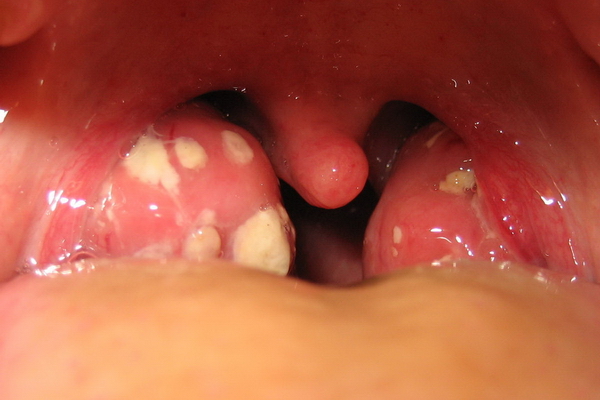

Запомните: когда белые пробки на миндалинах у ребенка заметны при визуальном осмотре горла, это означает, что они уже, образно говоря, проходят сквозь миндалины снизу доверху.

Начало образования пробок — в самой глубине лакун. Постепенно скопления этих масс, по консистенции напоминающих творог или переваренный рис, заполняют все пространство от дна к выходному отверстию. При сокращении мышц, при глотании, жевании, некоторое количество пробок выдавливается кверху, а основная масса, подобно базису айсберга, остается внизу, в толще миндалинных ниш.

На самом деле гнойных или казеозных пробок в лакунах миндалин у ребенка в три-четыре раза больше, чем кажется при взгляде на них со стороны открытого рта. Если пробки есть, то о ремиссии хронического тонзиллита не может быть и речи. С ними нужно бороться, не допускать их появления. Возникновение пробок — повод для немедленного обращения к ЛОР-врачу.